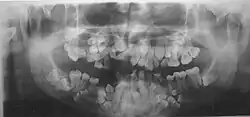

- Нарушения формирования корней, задержка в прорезывании молочных и постоянных зубов. Могут до 25-30-летнего возраста не меняться молочные зубы. Часто встречаются сверхкомплектные зубы.

Диагностика ключично-черепного дизостоза основана на клинических симптомах и рентгенологических исследованиях, которые включают изображения черепа, грудной клетки, таза и рук. Главный рентгенологический симптом — дефекты ключиц. Обычно отсутствует наружный (акромиальный) конец ключицы, в то время как внутренний (грудинный) конец присутствует. Но иногда ключица состоит из двух фрагментов. Полное отсутствие ключицы встречается редко.

- Удаление сверхкомплектных зубов.